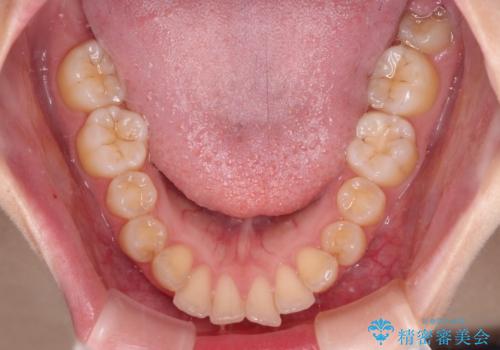

- 上下の前歯が突出しており、口が閉じにくいとのことで来院された患者様です。

上下前歯が著しく前突している状態であったので、上下左右の第1小臼歯4本を抜歯し、ワイヤー装置にて矯正治療を行うこととしました。

舌の突出癖があり、前歯の移動量も多くなるため、治療期間は長くなると予想されましたが、13ヶ月という予定の半分程度の期間で終えることができました。